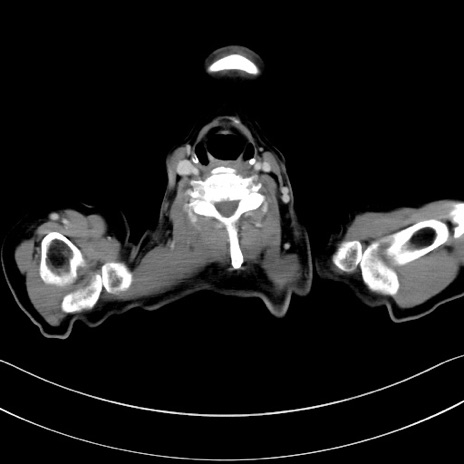

症例28(横断像)

【症例】60歳代男性

【主訴】嘔吐

【現病歴】胃癌にて胃全摘後。食思不振が悪化し、夜中に嘔吐することがある。

【既往歴】胃癌、胃全摘、脾摘、胆摘後

【データ】WBC 5900、CRP 10.56